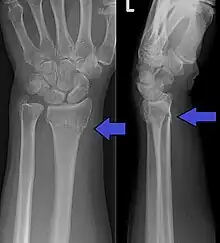

| A Colles fracture as seen on X-ray: It is a type of distal radius fracture. | |